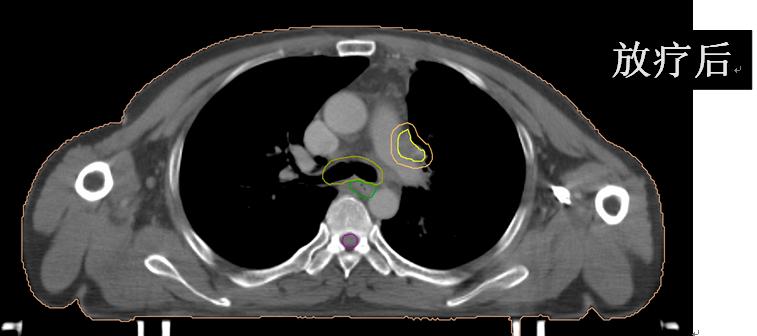

• (肺及纵隔病灶)iGTV1/GTV1/CTV1/70Gy/60Gy/50Gy/20F;

• (锁骨上病灶)GTV2/CTV2/60Gy/50Gy/20F。

放疗后患者咳嗽、咳痰、左肩背部疼痛、痰中带血、胸闷、气短完全缓解;继续于外院行综合治疗并定期随访观察。

有图有真相:放疗效果显著!是不是疗效好就应该损伤重呢?肺损伤?